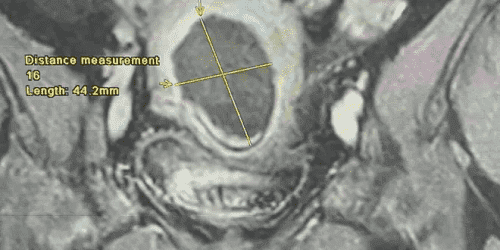

نبأ الأردن-أجرى فريق طبي متخصص من دائرة النسائية والتوليد ودائرة الاشعة برئاسة العميد الطبيب عامر غرايبة وأخصائي أول الاشعه تشخيصية الرائد الطبيب محمد حمدي الحياري في مدينة الحسين الطبية عملية كَي لورم ليفي رَحمي بحجم 7 سم مسبّب لنزيف رحمي مستمر و غزارة بالطمث.

وبين أخصائي أول الأشعة التشخيصية و التصوير التلفزيوني التداخلي الرائد الطبيب محمد حمدي الحياري أن العملية أجريت تحت التخدير الواعي و تحت توجيه جهاز التصوير التلفزيوني حيث تم إدخال مسبار الكَي داخل الورم الرحمي عبرة فتحة صغيرة في جدار البطن لا يتجاوز طولها ٣مم في وقت إجمالي بلغ 30 دقيقة دون مضاعفات وغادرت المريضة المستشفى بعد 24 ساعة من الإجراء.